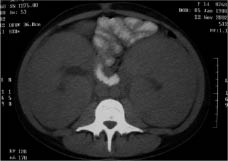

La presentación clínica de las LLA de estirpe T (un 15% del total de LLA) posee unos rasgos característicos. Los pacientes son, generalmente, de mayor edad y presentan recuentos leucocitarios mayores al diagnóstico. No es raro que estos niños debuten con una masa mediastínica (Fig. 2) y tienen una incidencia mayor de afectación del SNC al diagnóstico. En las figuras 3 y 4, se pueden observar otras manifestaciones clínicas de las LLA(7).

Figura 3. Niña de 14 años con LLA de estirpe T e infiltración renal masiva al diagnóstico.